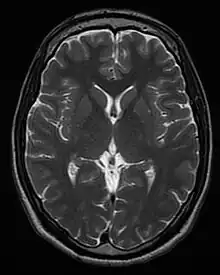

This axial T2-weighted (CSF white) MR scan shows a normal brain at the level of the lateral ventricles.

• T2-weighted (T2W) images: CSF is light, but fat (and thus white matter) is darker than with T1. T2-weighted images are useful for visualizing pathology.[26]